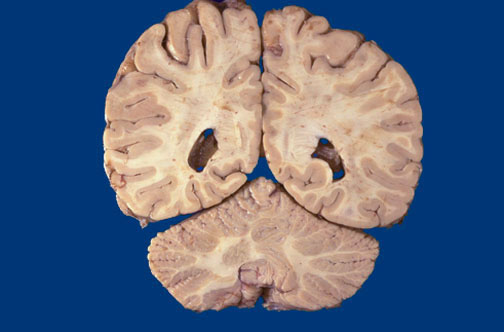

Identify the following regions of the normal brain in the image above: Occipital Lobe - Occipital horn, lateral ventricle - Cerebellum